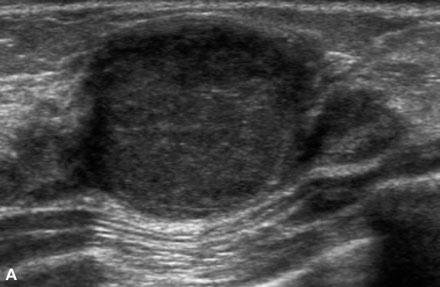

What is Fibroadenoma?

benign breast condition

Estrogen related tumor. Most common benign solid tumor of the breast.

Primarily in young women

What is the Sonographic Appearance of Fibroadenoma?

Oval

Gently lobulated

Hyperechoic

Uniform echogenicity

Smooth distinct borders

Wider than tall

Enhancement

Edge shadowing

Arise from TDLU

Pseudo-encapsulated

What are the presentations of Fibroadenoma?

Painless palpable mass, firm rubbery